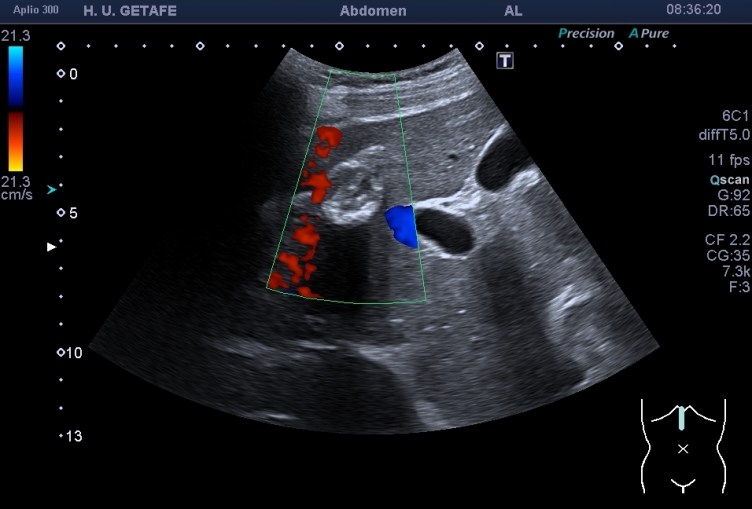

Una de ellas, la primera, era mucho más hiperecogénica y más pequeña, su centro estaba mas calcificado, su sombra acústica posterior era mucho más acuciada y llamaba más la atención. Justo al lado, otra lesión de mayor tamaño, su calcificación era mucho más sutil y más periférica delimitando una LOE hipoecogénica de un tamaño muy importante, adyacente a la más pequeña, como he comentado previamente. Ambas sin señal Doppler.